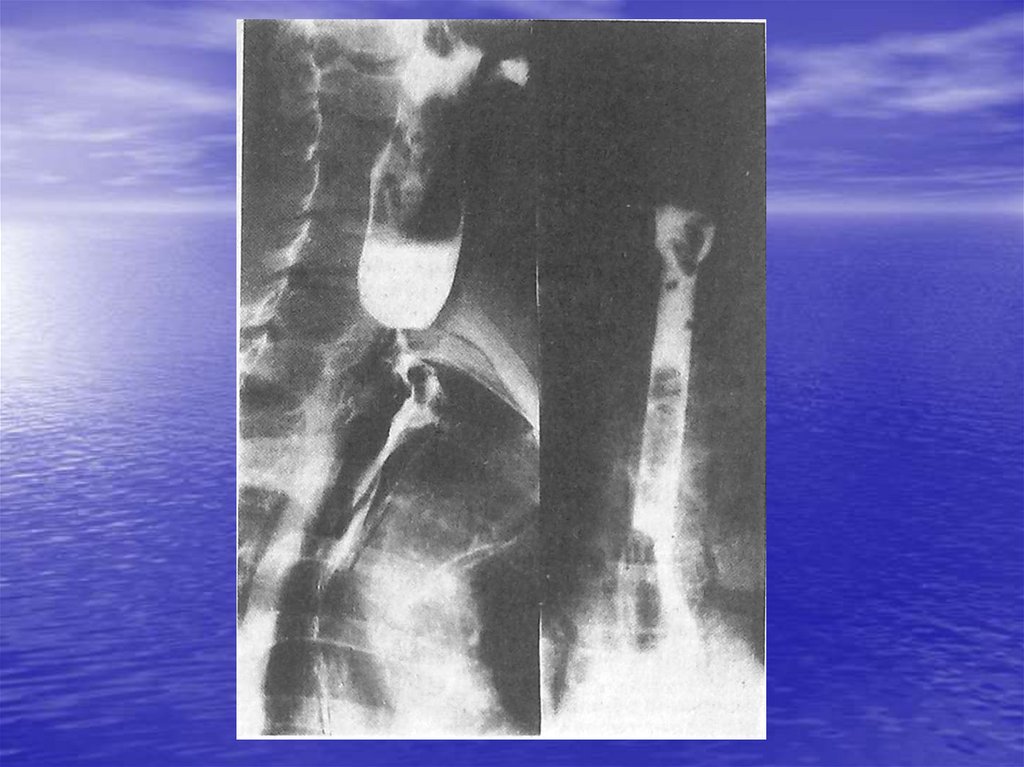

А) Перфорация стенки пищевода

В) Спонтанный разрыв пищевода

• 4. Химические ожоги и рубцовые сужения

• А) Химические ожоги пищевода